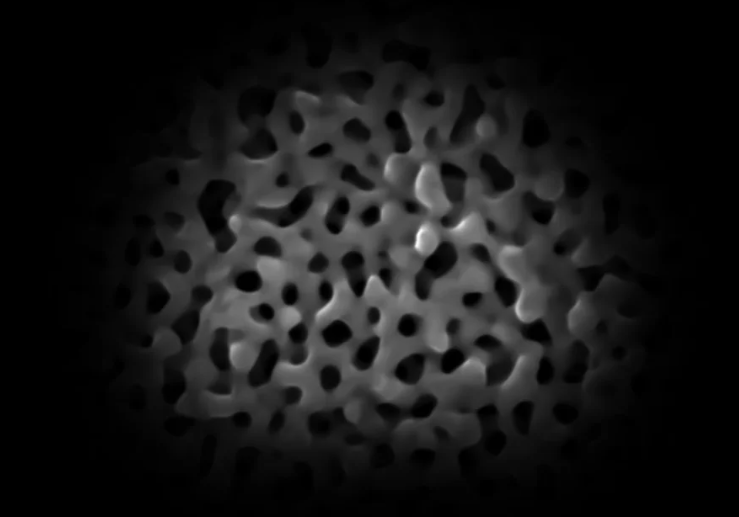

Një pamje cerebrale e një trurit të rritur në mënyrë sintetike. Kjo mini kopje e organit është më e vogël se një thjerrëz dhe përfaqëson në mënyrë të përkryer lidhjet e ndërlikuara të trurit të njeriut në zhvillim.